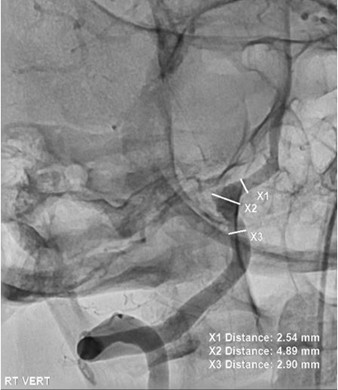

The patient underwent cerebral angiogram demonstrating a dilation of the right vertebral artery in the distal V4 segment just before and proximal to the vertebrobasilar confluence and centered in the region of more prominent hemorrhage on initial scans findings consistent with a ruptured dissecting aneurysm (Figure 5).

Figure 5. Cerebral angiogram demonstrating a dissecting aneurysm in the right vertebral artery V4 segment.